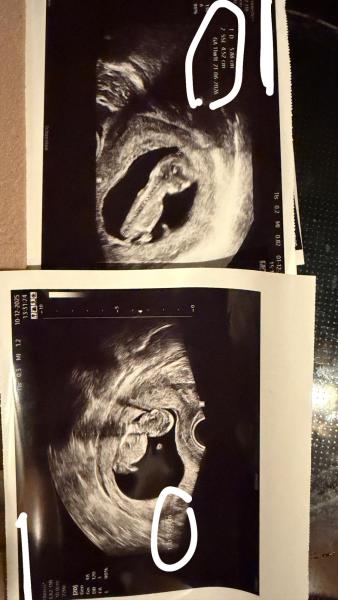

Hallo, ich war heute beim FA und dieser meinte alles okay. Jetzt frage ich mich, kann ein Arzt auch mal falsch schauen und das Herzchen schlägt doch nicht? Bin in der 12 SSW (11+5) ich habe es nämlich nicht gesehen..  Was mich wundert ich war an 10+3 dort und da stand 4,3cm und heute bei 11+5 stand 4,5cm.. Das hat mich später voll verwirrt, aber ich finde auf den Bildern liegt das Baby jeweils auch total anders. Kann es sein das es dann so wenig "wächst"? Ich sehe gerade das von heute die Beschriftung nur "D" ist nicht SSL. Aber wieso ist das D im ersten Bild von den cm deutlich größer als heute ? Ich hänge mal beide Bilder an. Bitte keine doofen Kommentare.. LG

Ja sie meinte ein Herzschlag sieht man auch, aber das Baby hat sich eig nicht wirklich bewegt, deswegen kam mir So die Frage auf, ob die sich auch vergucken können. Und letzte Mal stand dort "D" 5,86 cm da war ich bei 10+3 und gestern bei 11+5 stand dort "D" 4,53 cm Das D ist aufjedenfall nicht die Länge des Babys, das weiß ich. Ich frage mich nur was ist das und wieso ist es 1cm kleiner.

Und wenn ich mir beide Bilder angucke, liegt es beim ersten Bild ja doch sehr gestreckt, beim zweiten bisschen zusammen gekuschelt.  Ich glaube wirklich, dass es an der Lage des Mäuschens gelegen hat 🩷